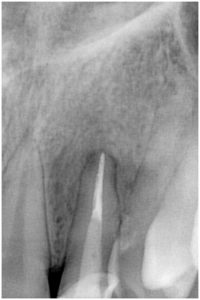

3枚目の写真が約半年後の画像です。根の先の黒い陰が無くなっていますね。

このように、たいてい根の治療をきちんとすることで、根尖病巣は治ります。しかし、人間の治癒力って本当にすごいですね。